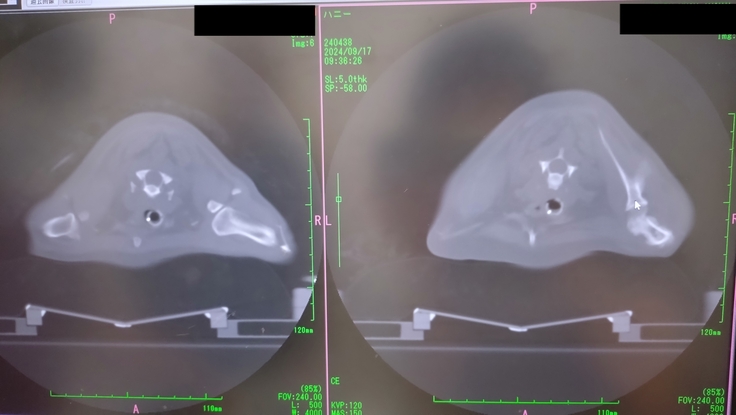

この日はまたCTを撮り、扁桃腺とリンパ節に4回目の放射線の照射をした。

CTで、扁桃腺とリンパ節に転移した腫瘍はかなり小さくなったのが分かったけど、右前足の付け根の骨に転移が見つかってしまいました😭

この日は既に、扁桃腺とリンパ節への放射線照射は終わっていたので、午後の予約の合間で骨転移の部分の放射線照射もやっていただけることになった。全身麻酔を1日で2回もすることになりそれも心配だった。

先生からは、骨転移があるということは、全身にも回っている可能性が高い。そうなるといたちごっこでどこまで放射線をやってあげるかだと。骨転移し、状況が変わったので、今回、骨転移部分は腫瘍を小さくする目的ではなく、痛みを取るための緩和的照射のみをやりますと。今後は、痛みが治まらなかったり、痛みが出てきた所に緩和的照射を行っていきましょうと。